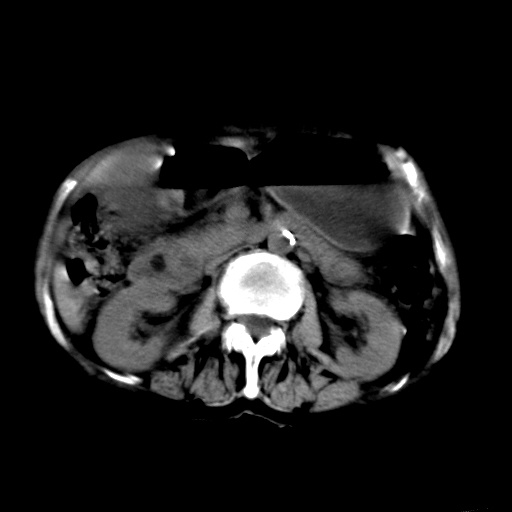

以下是引用杀毒软件在2009-3-4 17:38:00的发言:[br]为何没有喝照影剂呀? 胆总管及肝内胆管扩张,增强吧。[br][br]考虑-----十二指肠占位----建议----十二指肠镜检查[br][br]

以下是引用jiangjing在2009-3-4 17:45:00的发言:[br]低位胆道梗阻。十二指肠降段局部管壁增厚。扫描效果不理想,建议ct增强及ercp。

以下是引用杀毒软件在2009-3-4 17:38:00的发言:[br]为何没有喝照影剂呀? 胆总管及肝内胆管扩张,。增强吧。[br][br]考虑-----十二指肠占位----建议----十二指肠镜检查[br][br][br][br][本贴已被 杀毒软件 于 2009-3-4 17:56:38 修改过]